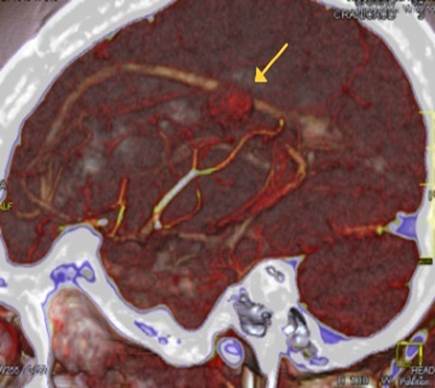

Se le realiza tomografía axial computarizada (TAC) de cráneo simple y E/V, donde se observa imagen hiperdensa, redondeada con aspecto de ovillo con densidad de 54 UH, localizada a nivel del lóbulo parietal izquierdo (Figura 1 a, b, c) y angio-TAC de cráneo donde se observa imagen hiperdensa (54 UH), redondeada con aspecto de ovillo, localizada a nivel del lóbulo parietal izquierdo en territorio de la arteria cerebral media y con drenaje a nivel del seno sagital inferior (Figura 2).

Figura 2: Angio-TAC de Cráneo secuencia sagital. Fuente: Servicio de Imagenología del Hamad General Hospital